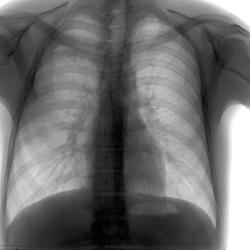

Пол пациента: Мужской пол Тип патологии: Норма, варианты нормы Область исследования: Скелетно-мышечная система Методы исследования: Rg Молодой человек. Очередная плановая ФГ. Просто посмотреть как бывает)))) ID:33439 Mon, 18/11/2013 - 16:30 #1 Любовь С. Offline Last seen: 9 years 10 months ago Joined: 23.12.2010 - 01:58 Posts: 2324 Ой, какой Люшкизм))) а переломы были или всё своё, родное?) "Предоставляя весь смысл и совершенство в распоряжение одного только Бога, вы избавляете себя от бездны хлопот." Джон Уитборн. Mon, 18/11/2013 - 17:37 #2 stovbav Offline Last seen: 2 years 7 months ago Joined: 20.12.2009 - 17:28 Posts: 7066 Любовь С. wrote: Ой, какой Люшкизм))) а переломы были или всё своё, родное?) Родное))), только там и задние отрезки "звучат")))) Болезни ног: виды, симптомы, причины, профилактика и лечение Mon, 18/11/2013 - 19:30 #3 Сергей Кузьминов Offline Last seen: 1 year 5 months ago Joined: 06.10.2012 - 15:51 Posts: 11813 Надеемся,патологию не нашли.А то,бывает.